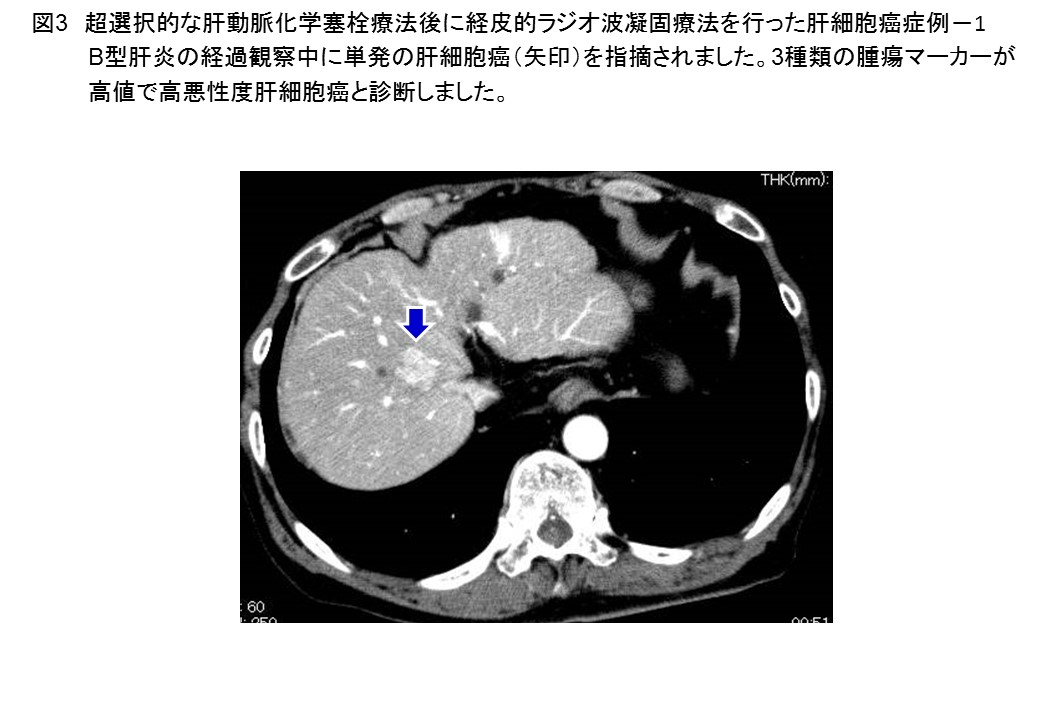

肝細胞癌に対する肝切除、局所焼灼療法、肝動脈・門脈塞栓療法、薬物療法のすべてに対応可能です。血管造影下治療や薬物治療については別項を参照ください。肝移植や放射線治療は熊本大学附属病院と連携して行っています。局所焼灼療法は経皮的な手技ばかりでなく、腹腔鏡や胸腔鏡による治療が可能なことが特徴です(図2)。超選択的な肝動脈化学塞栓療法後に経皮的ラジオ波焼灼療法を行った高悪性度肝細胞癌症例(図3, 4)を提示します。効果判定は、造影エコーや造影CTによる3次元画像により確実に行います。最近、肝動脈門脈短絡を伴う巨大肝細胞癌に対する肝動脈化学塞栓療法とレンバチニブによる分子標的治療後のコンバージョン肝切除症例を経験し、報告しました (Sato N, Beppu T, et al. Anticancer Res 2019) (図5-10)。肝切除後に100万を超える腫瘍マーカー (AFP)は正常化しました。C型肝炎の治療も終了し、治療開始後7年間再発なく元気にされています。このような肝癌の薬物療法施行例も年々増加しています(図11)。